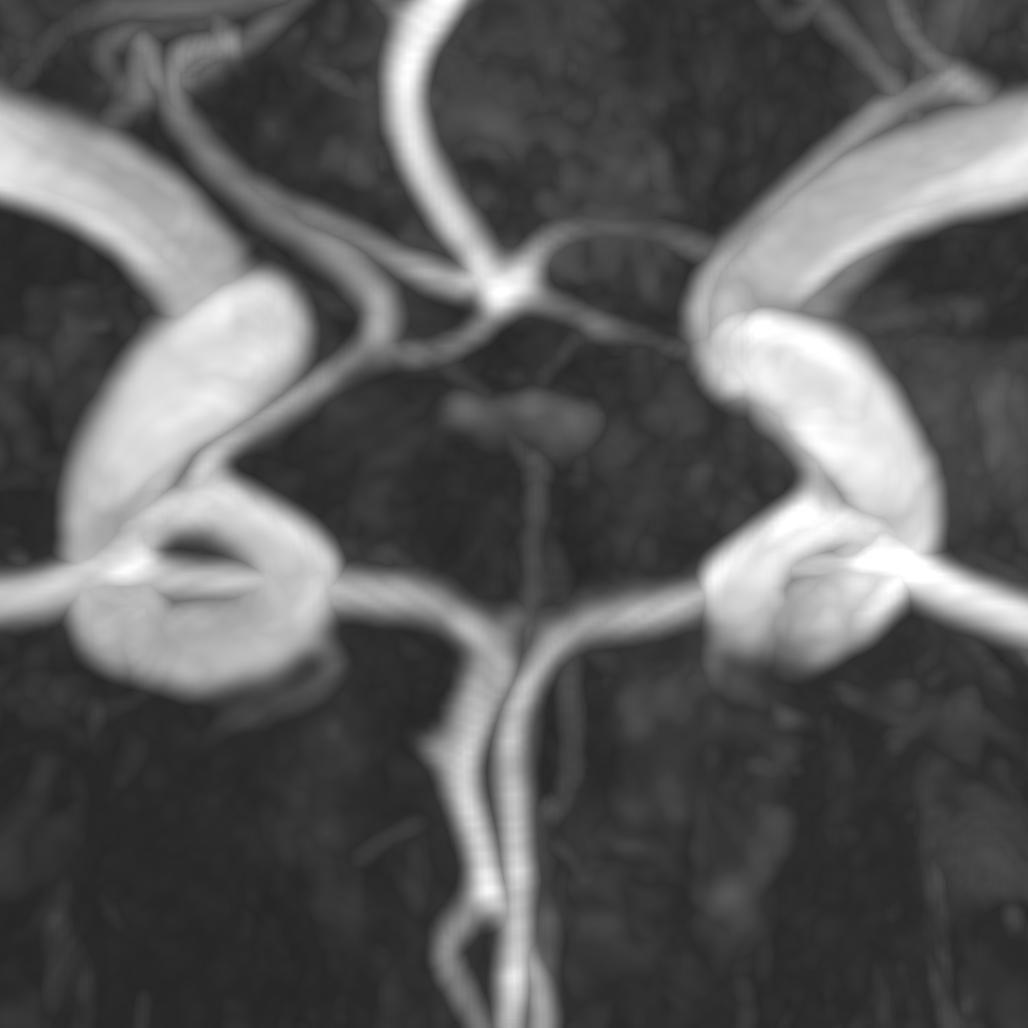

| TopCoW[40] | 3D | multi-class | 200 | Circle of Willis vessels in the brain |

We employ five public datasets featuring thin structures for validating the proposed Skeleton Recall Loss. The datasets span natural as well as medical images, covering a range of segmentation challenges, including both binary and multi-class segmentation problems in 2D as well as 3D contexts. An overview of the datasets can be found in Tab. 1. Among the three 2D datasets used in this study, the Digital Retinal Images for Vessel Extraction (DRIVE) dataset [32] was employed, focusing on retinal vessel segmentation. Additionally, structural inspection images designed for concrete crack segmentation (Cracks) [36] and aerial images of Massachusetts for road segmentation (Roads) [21] were included, highlighting the diversity of thin structures in natural and constructed environments. In the 3D domain, we incorporated two cutting-edge medical image segmentation challenge datasets. One of them was ToothFairy111https://toothfairy.grand-challenge.org/, which was a segmentation challenge on 3D Cone-Beam CTs [6, 5] featuring the inferior alveolar canal as the target structure. Additionally, the TopCoW222https://topcow23.grand-challenge.org/ dataset for topology-aware 3D segmentation of vessels in the Circle of Willis for CTA and MRA data [40] was utilized, encompassing binary as well as multi-class segmentation on 13 different subtypes of vessels. This diverse set of datasets enables a comprehensive evaluation of the proposed Skeleton Recall Loss, demonstrating generalizability of the method to a wide range of thin structure segmentation challenges in both 2D and 3D contexts.

Binary segmentation has historically sufficed for many image analysis tasks across various domains. However, as the demand for finer-grained analysis grows, transitioning to multi-class segmentation becomes increasingly vital. This shift is especially pertinent in medical contexts due to the prevalence of thin structures where binary segmentation may not adequately capture the complexity of anatomical features. For instance, the recent TopCoW challenge[40] revealed that binary segmentation of brain vessels can be deemed as sufficiently solved, approaching inter-rater agreement in the Dice score. However, differentiating between the different vessels still remains a challenging task. Our Skeleton Recall Loss demonstrates powerful multi-class segmentation capabilities in addition to standard binary settings. Tab. 2 showcases the results of multi-class segmentation on 13 different brain vessel classes of the TopCoW dataset using both standard nnUNet and our proposed Loss. The results demonstrate that while nnUNet exhibits slightly better error, our Skeleton Recall Loss significantly improves Dice and clDice scores. Moreover, it performs on par in terms of error, ultimately yielding a superior overall result.